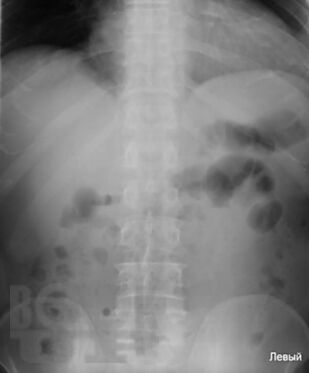

Учебное пособие разработано в соответствии с требованиями ФГОС ВО в рамках рабочей программы модуля «Госпитальная хирургия» дисциплины «Госпитальная хирургия, детская хирургия» и дисциплины «Неотложные состояния в хирургии» для обучающихся по специальности 31.05.01 «Лечебное дело». В пособии представлены наглядные изображения различной патологии органов грудной клетки и брюшной полости. Отражены методы лучевой диагностики: рентгенография, рентгеноскопия с контрастированием, компьютерная томография, эндоскопическая ретроградная холангиопанкреатография. В учебном пособии использованы оригинальные снимки, предоставленные коллективом авторов.